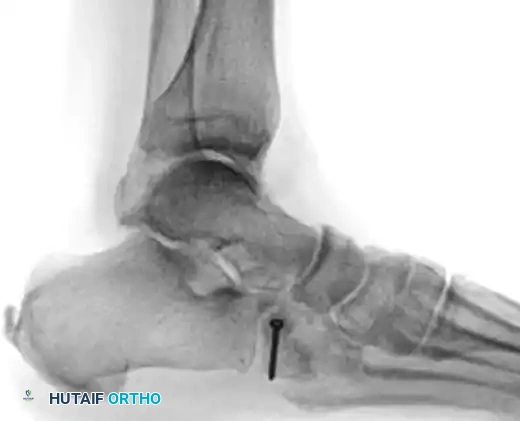

Radiographic Evaluation:

Standard non-weight-bearing radiographs often miss subtle instability. Weight-bearing radiographs are absolute requirements if the patient can tolerate them. If the patient cannot bear weight, a short-leg cast should be applied for 10-14 days, followed by repeat weight-bearing films.

Key radiographic parameters to evaluate:

1. The medial shaft of the 2nd metatarsal must align perfectly with the medial aspect of the middle cuneiform on the AP view.

2. The medial shaft of the 4th metatarsal must align perfectly with the medial aspect of the cuboid on the oblique view.

3. The 1st metatarsal-cuneiform articulation must show no incongruency.

4. The "Fleck Sign": Look for a small bony avulsion in the space between the medial cuneiform and the base of the 2nd metatarsal. This represents a bony avulsion of the Lisfranc ligament.

5. Evaluate the naviculocuneiform articulation for subtle subluxation.

If plain radiographs are equivocal but clinical suspicion remains high, CT imaging is excellent for identifying occult fractures, while MRI is the gold standard for evaluating the integrity of the Lisfranc ligament complex.